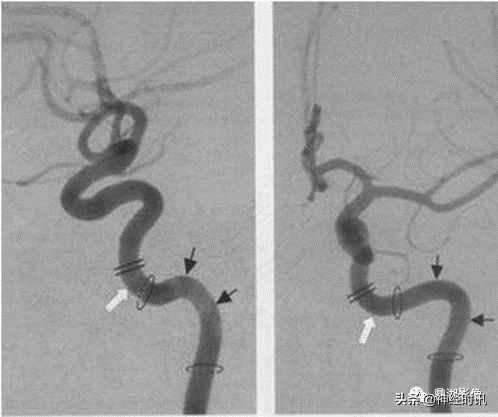

各种颅内出血